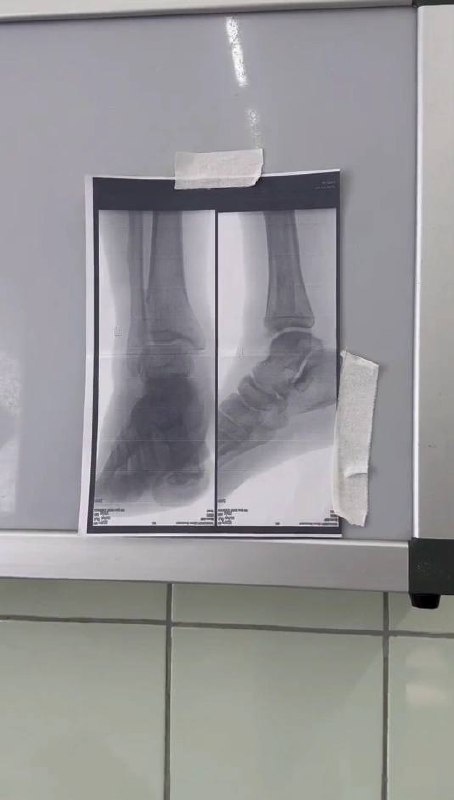

В больнице скорой медицинской помощи Новочеркасска рассказали о клиническом случае, связанном с гололёдом. Пациент, поскользнувшийся на улице, обратился за помощью лишь спустя двое суток после падения.

В результате обследования у него был диагностирован изолированный перелом наружной лодыжки со смещением. Травматологи-ортопеды Рамин Ибрагимов и Николай Любимов успешно провели операцию остеосинтеза, установив титановую пластину и винты.

Послеоперационный период прошёл без осложнений. На данный момент пациент уже выписан из стационара и будет продолжать лечение амбулаторно в поликлинике.